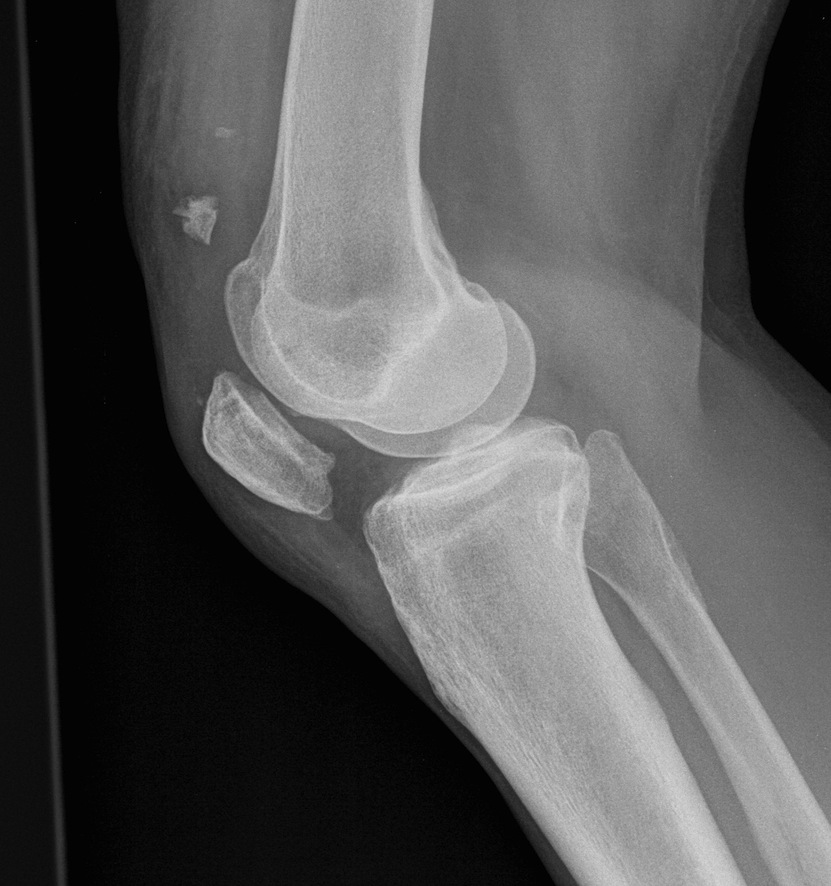

Xray

Patella Baja